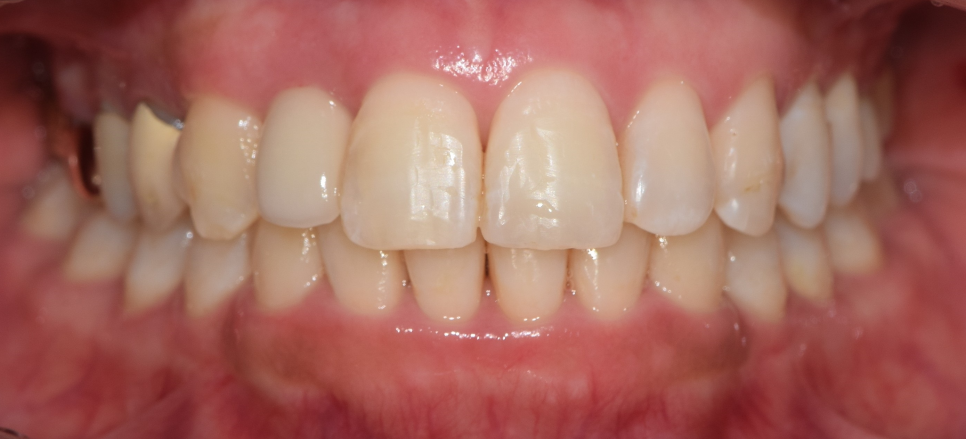

이제 최종 결과를 보여드리겠습니다.

이제, 흡잡을 곳이 없군요.

교정치료 및 발치와보존술, 임플란트 시술의

복합 결과를 보고 있으며 3년이라는 긴 기간이

소요되어서 원래의 구강 내 상태를 되찾아드렸네요.

아래 내용에서, 얼마나 변화가 되었는지를

한 눈에 살펴보실 수 있으며

"3년간의 f.u 및 변화"